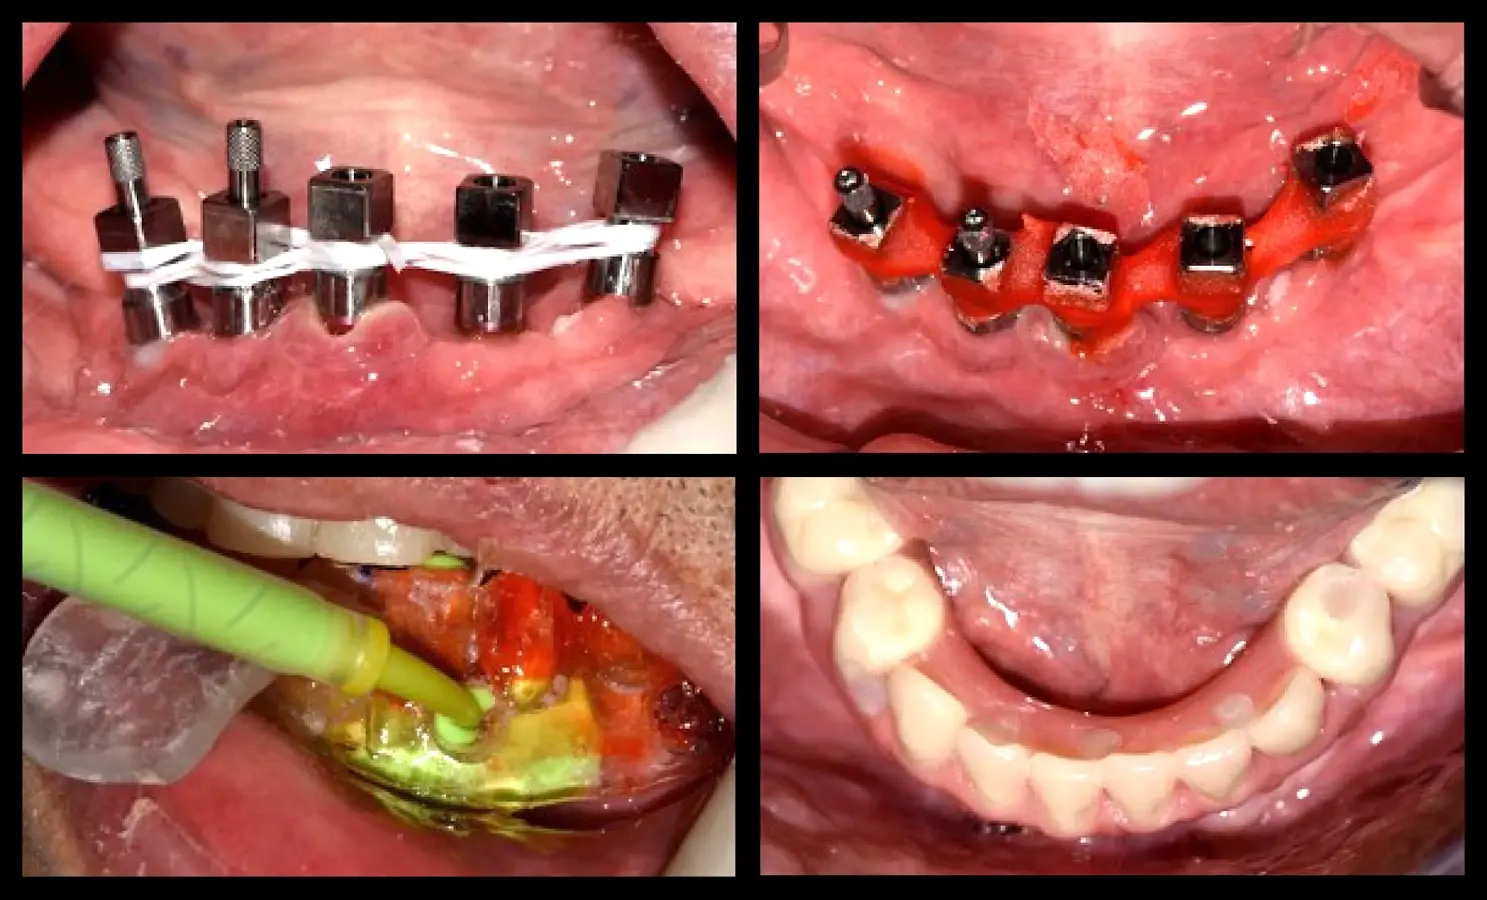

Paciente de ochenta y dos años de edad, de sexo masculino, acudió a la consulta odontológica refiriendo la necesidad de una prótesis inferior y malestar con la prótesis fija superior maxilar. El paciente refirió que le diagnosticaron diabetes mellitus tipo 2 hace 15 años. Refirió también haber tenido carcinoma de próstata y haber recibido radioterapia, hormonoterapia y orquiectomía. La última dosis de radioterapia la había recibido hace 72 meses y fue de 78 Gy en total. El paciente tenía un ASA2 según la clasificación del estado físico de la Sociedad Americana de Anestesiología (ASA)8,9. Asímismo, autorizó la recolección de la información y el uso de fotografías para su publicación con la firma de un consentimiento informado. En la evaluación intraoral, se observó coronas metal cerámicas tipo veneer en las piezas superiores con mala adaptación, acúmulo de placa bacteriana y edentulismo mandibular. Se inició el tratamiento con la motivación e instrucción de higiene oral, se procedió con la eliminación de las bolsas periodontales mediante raspado y alisado radicular. Estabilizada la salud periodontal, se realizó el alargamiento de las coronas clínicas. La gingivectomía se realizó con el electrobisturí (Servotome, Acteon), mientras que para el remodelado óseo se utilizaron los insertos P2LD del piezoeléctrico (Piezomed, W&H) (Figura 2).

Recontorneo gingival

Figura 2. Recontorneo gingival y alargamiento de corona clínica mínimamente invasiva mediante cirugía piezoeléctrica, donde se remodela el hueso sin elevar grandes colgajos (a). Se utilizaron los insertos de piezoeléctrico P2LD de W&H (b).

El procedimiento quirúrgico se inició con la asepsia y antisepsia del campo operatorio y del paciente. A continuación, se colocó anestesia infiltrativa a nivel de la proyección de salida de los agujeros mentonianos, se procedió con la incisión y decolado. Se realizó la delimitación y regularización del reborde óseo mediante el inserto aserrado B7 y el subsiguiente remodelado del reborde crestal mediante el inserto plano diamantado S1 del piezoeléctrico Piezomed (W&H) (Figuras 4 y 5).

Remodelado óseo

Figura 4. Remodelado óseo mínimamente traumático realizado con tecnología piezoeléctrica.

La segunda fase quirúrgica y colocación de pilares intermedios fue realizada en la semana 18, siguiendo la recomendación del fabricante con un torque de 20 Ncm. Se realizó la impresión del maxilar superior y la transferencia de los implantes del maxilar inferior. Una vez corroborado el asentamiento de ambas estructuras en boca se envió al laboratorio para el enfilado de la estructura inferior. Finalizada la prótesis fue instalada en el paciente (Figura 10).

Rehabilitación fina

Figura 10. Rehabilitación final: toma de impresión mediante la técnica de la guía multifuncional.